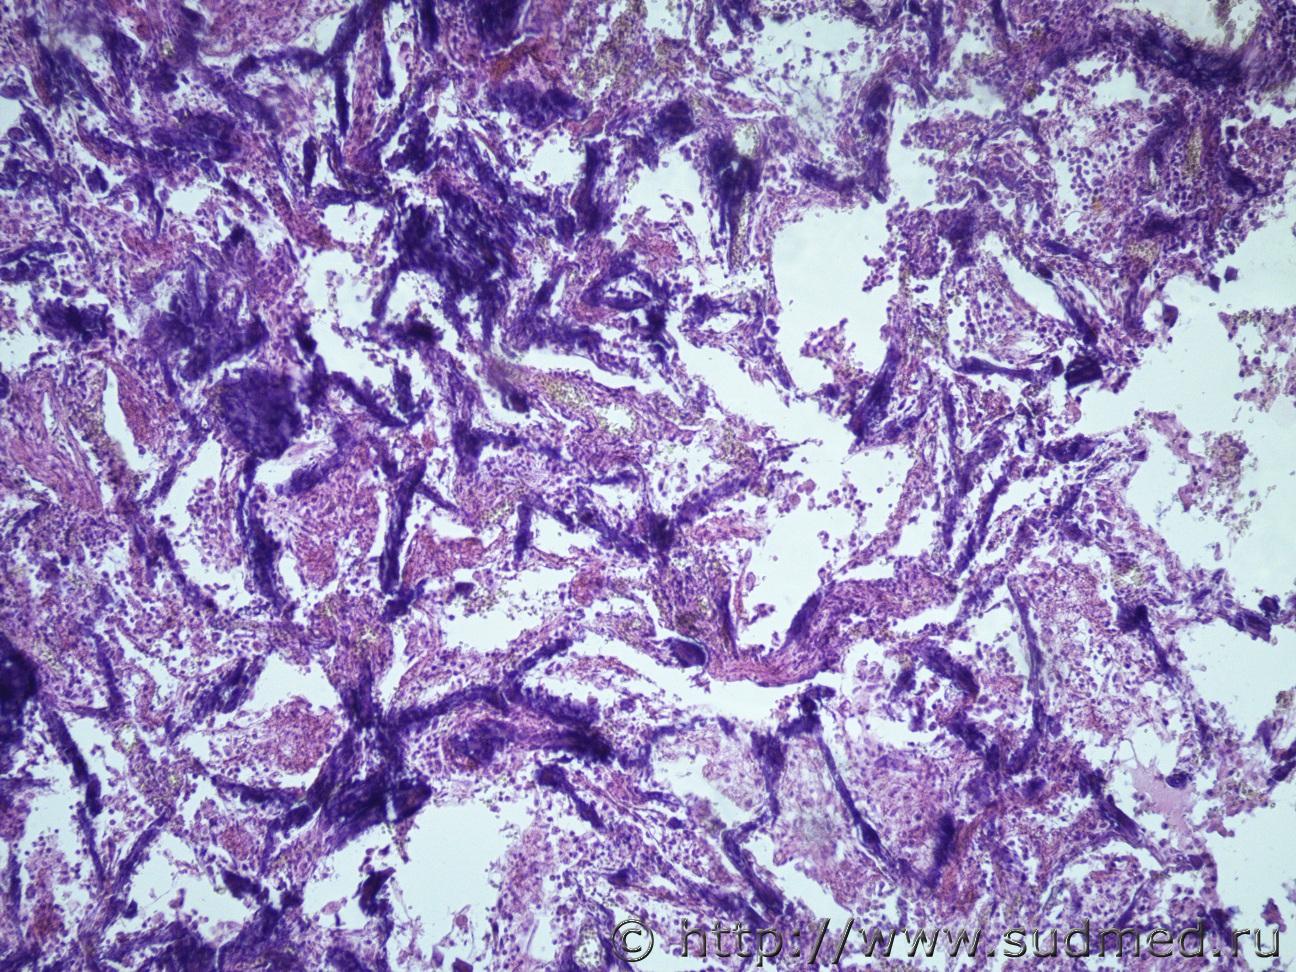

Ув. коллеги, нужна помощь, что это за заболевание легких? В атласе патологическая анатомия легких, нет не чего похожего. Это какое то диффузное паренхиматозное заболевание?. Жен 46 лет. Макро- Воздушность ткани верхних долей легких снижена, легочная ткань сиреневой окраски, образования диффузного характера беловато-сероватого цветы, плотные. По всем препаратам межальвеолярные перегородки инкрустированы известью. В просвете альвеол фибрин, лейкоциты, макрофаги.

Медик В просвете альвеол в основном мицелий грибов. 12.08.2019 - 21:49

Медик На втором фото похоже на ИФА (такие изменения могу... 12.08.2019 - 21:56

Медик Петрификаты в межальвеолярных перегородках могут б... 12.08.2019 - 22:04

доктор морфолог Уважаемый Медик, как всегда в точку попадает. Это ... 14.08.2019 - 20:49